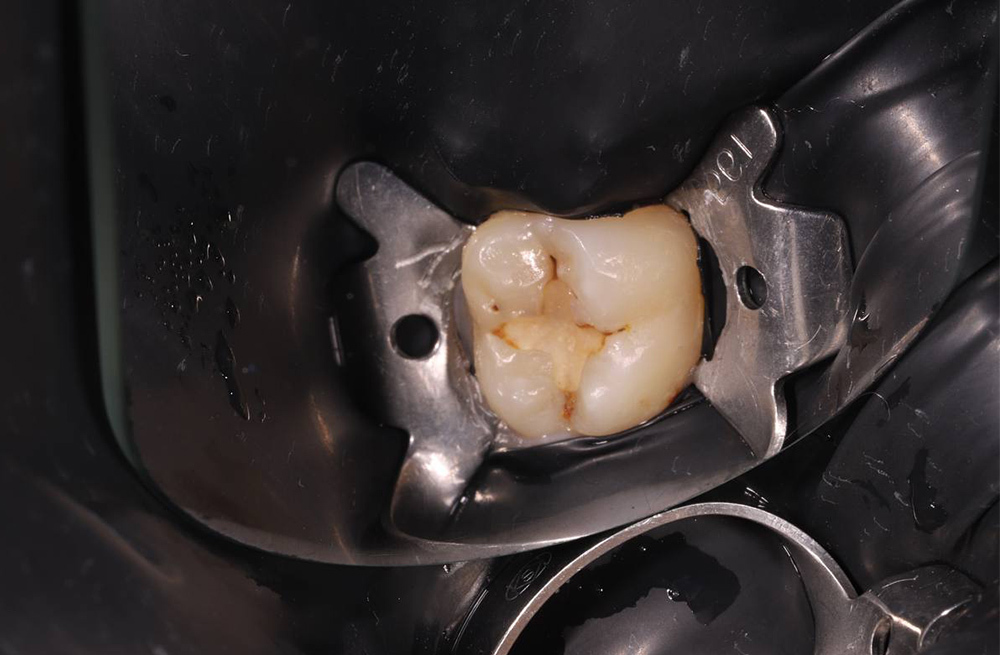

Препарирование и реставрация 36 зуба при вторичном кариесе с надежной изоляцией и полировкой пломбы